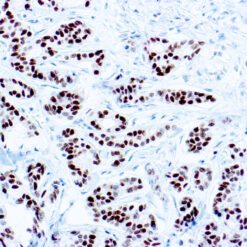

CD7 is expressed by most peripheral blood T cells, NK cells, and all thymocytes. It is one of the earliest surface antigens on T and NK-cell lineages. The antibody is a useful aid for classification of T-cell malignancies.

| Cellular Localization | Cell surface/membrane |

| Positive Control Tissue | Tonsil |